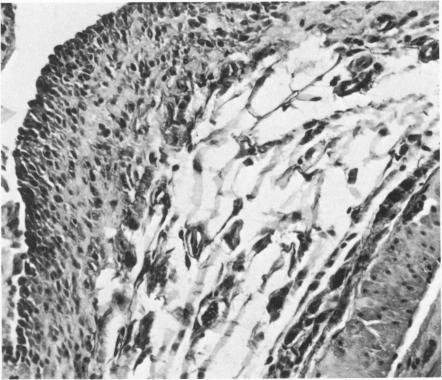

Malignant mesotheliomas were induced in the rat peritoneum by a single injection of chrysotile or crocidolite asbestos fibers. The immediate toxicity of the fibers was noted in both groups of animals, producing approximately 40% mortality, within 8 days after the injection associated with acute peritonities. Tissue reactions to these two types of asbestos were significantly different. Crocidolite fibers were easily seen by light microscopy, in the tissue sections throughout the period of study, and they produced foreign-body giant cell granulomas. However, giant cells were not seen in chrysotile granulomas, and the asbestos fibers were only seen by electron microscopic study. They appeared to be coated by a protein-like substance. During earlier stages of tumorigenesis, the epithelioid and/or mixed cell type mesotheliomas seemed to have no specific relationship to granulomas, but pure spindle cell tumors were seen to develop in close relationship to granulomas, and they appear to be fibrosarcomas. Electron microscopic and histochemical methods were used to define the morphologic characteristics of the tumor cells. The formation of hyaluronic acid was found in cells of the epithelioid type, contrasted with extracellular accumulation in the spindle cell tumors.

通过单次注射温石棉或青石棉纤维在大鼠腹膜中诱发恶性间皮瘤。两组动物均出现纤维的即时毒性,注射后8天内产生约40%的死亡率,伴有急性腹膜炎。对这两种类型石棉的组织反应显著不同。在整个研究期间,在组织切片中通过光学显微镜很容易看到青石棉纤维,它们产生异物巨细胞肉芽肿。然而,在温石棉肉芽肿中未见巨细胞,石棉纤维仅通过电子显微镜研究才能看到。它们似乎被一种蛋白质样物质包裹。在肿瘤发生的早期阶段,上皮样和/或混合细胞型间皮瘤似乎与肉芽肿没有特定关系,但纯梭形细胞瘤与肉芽肿密切相关,且它们似乎是纤维肉瘤。使用电子显微镜和组织化学方法来确定肿瘤细胞的形态特征。发现上皮样细胞类型的细胞中形成透明质酸,这与梭形细胞瘤中的细胞外积累形成对比。